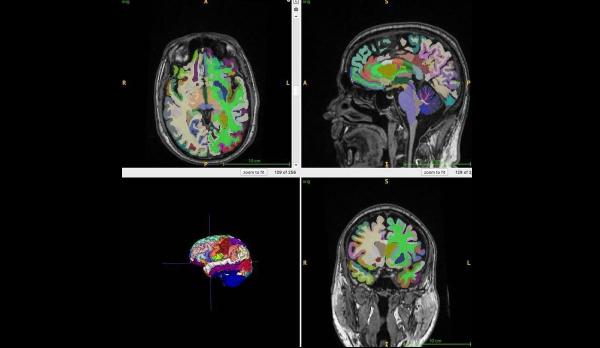

Во время исследования, которое сейчас еще продолжается, ученые обследовали с помощью МРТ тела 1164 здоровых человек из четырех клиник. Женщин среди них было 52%. Средний возраст участников — 55,17 года. Ученые использовали Т1-взвешенные последовательности. При использовании этого метода, жир на МРТ-снимках выглядит светлым, а жидкость — темной. Это помогает оптимально визуализировать мышечную, жировую и мозговую ткани. Алгоритм искусственного интеллекта авторы использовали, чтобы количественно оценить общий нормализованный объем мышц, висцерального жира на животе, подкожного жира и возраста мозга.